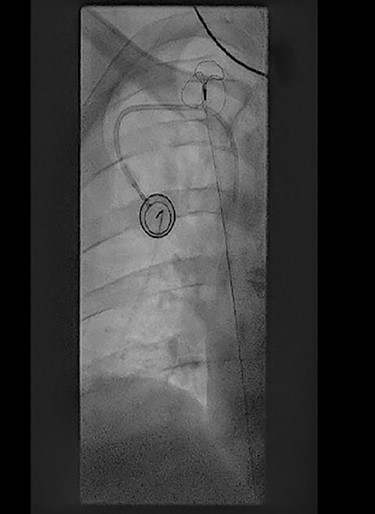

Perioperative fluoroscopy during removal of fibrin sheaths with a snare.